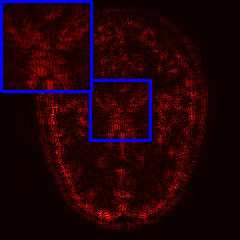

Limited by imaging systems, the reconstruction of Magnetic Resonance Imaging (MRI) images from partial measurement is essential to medical imaging research. Benefiting from the diverse and complementary information of multi-contrast MR images in different imaging modalities, multi-contrast Super-Resolution (SR) reconstruction is promising to yield SR images with higher quality. In the medical scenario, to fully visualize the lesion, radiologists are accustomed to zooming the MR images at arbitrary scales rather than using a fixed scale, as used by most MRI SR methods. In addition, existing multi-contrast MRI SR methods often require a fixed resolution for the reference image, which makes acquiring reference images difficult and imposes limitations on arbitrary scale SR tasks. To address these issues, we proposed an implicit neural representations based dual-arbitrary multi-contrast MRI super-resolution method, called Dual-ArbNet. First, we decouple the resolution of the target and reference images by a feature encoder, enabling the network to input target and reference images at arbitrary scales. Then, an implicit fusion decoder fuses the multi-contrast features and uses an Implicit Decoding Function~(IDF) to obtain the final MRI SR results. Furthermore, we introduce a curriculum learning strategy to train our network, which improves the generalization and performance of our Dual-ArbNet. Extensive experiments in two public MRI datasets demonstrate that our method outperforms state-of-the-art approaches under different scale factors and has great potential in clinical practice.